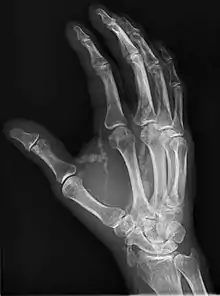

| Hand radiograph showing tumoral calcinosis, PA radiograph of the right hand showing tumoral calcinosis-like metastatic calcification in a patient on dialysis. Dialysis alters calcium phosphate product (>70). Idiopathic tumoral calcinosis is autosomal dominant and is not associated with dialysis. Note the premature arterial calcification which is a clue that this is a renal patient. Vascular calcification contributes to an increase in morbidity. |